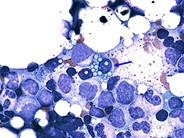

Multiple Myeloma - 3.

Category: Lymphoma: Mature B-cell and Plasma cell Neoplasms > Plasma Cell Neoplasm

These plasma cells have basophilic cytoplasm with a prominent centrosome.